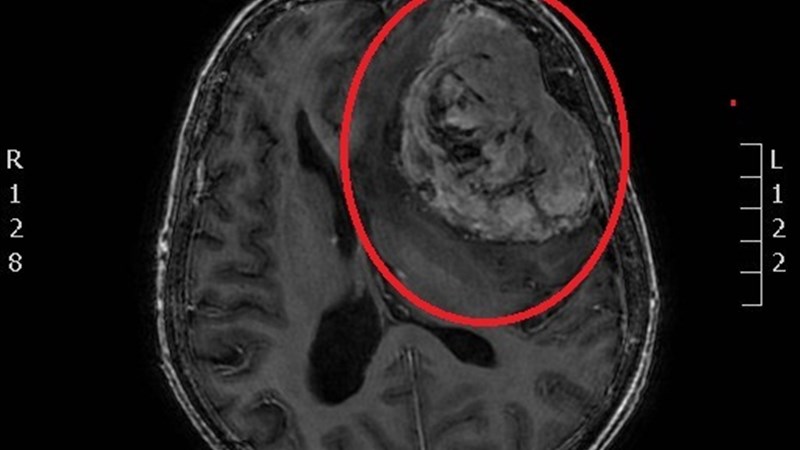

Опухоль мозга лобной доли

Опухоль мозга лобной доли 113 фотографий